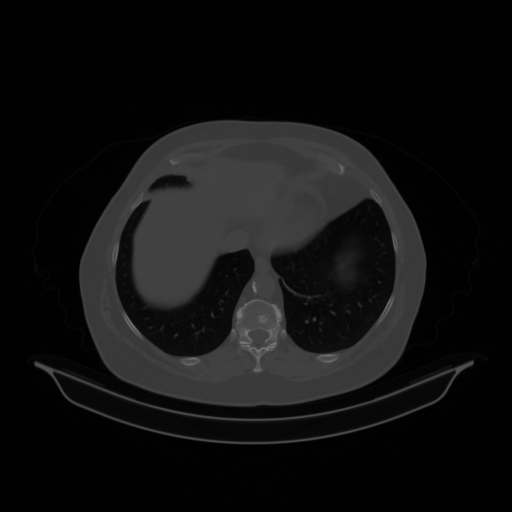

Slice 70 Targeting Evaluation

Slice: Slice_70

Conversion: NATIVE β†’ VENOUS

Targeted Slice 70 - Lung Window Analysis (Generated vs Real Venous)

0.797

Lung SSIM

87.2

Lung RMSE

35.8

Lung MAE

Generated VENOUS CT scan (A→B translation)

No window - Raw intensity values

Lung window (WL -600, WW 1500 β†’ Low βˆ’1350, High +150)